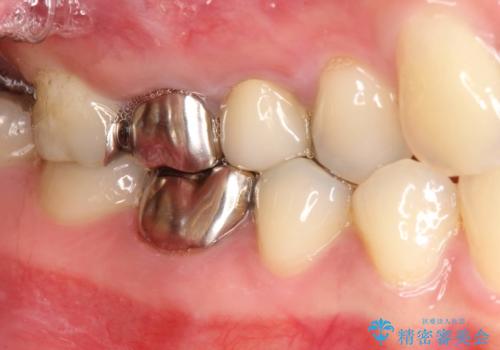

[深い虫歯] 根管治療・歯周外科治療を行い歯を保存する

![[深い虫歯] 根管治療・歯周外科治療を行い歯を保存するの症例 治療前](https://seimitsushinbi.jp/wp/wp-content/uploads/2019/10/565cd81632432c46200480d3f4728f8d-500x350.jpg?v=1572444569)

![[深い虫歯] 根管治療・歯周外科治療を行い歯を保存するの症例 治療後](https://seimitsushinbi.jp/wp/wp-content/uploads/2019/10/f94f918301554464d21b1fb7c0a3d93b-500x350.jpg?v=1572444693)